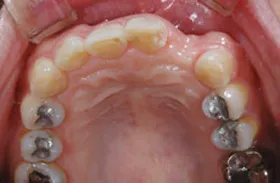

生まれつき歯が生えてこなかったケース

■治療前:生まれつき下顎左右前歯がなく隙間がある

■治療後:矯正治療後、下顎左右3番の2本にインプラント治療

| 主訴 | 生まれつき歯がなく隙間があり、審美障害・咀嚼機能障害がある |

| 治療方法 | インプラント治療 + 矯正治療 |

| 治療期間 | インプラント治療 約6ヶ月 |

| 通院回数等 | インプラント治療 約6回 |

| 費用 | 約94万円(税込) |

| リスク・副作用 | 術後の腫れ・痛み |